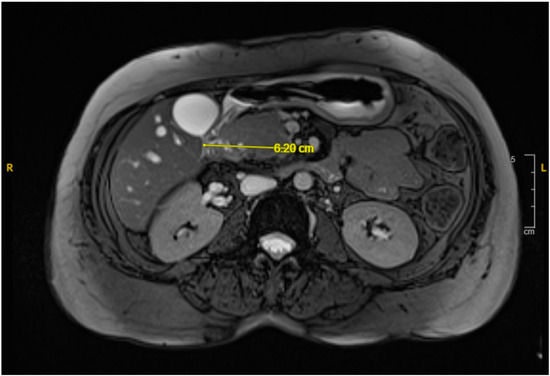

Background and Clinical Significance: Perforation of the left ventricle related to microaxial ventricular assist devices (Impella) is a rare but fatal complication related to placement or adjustment. It results in left ventricular hemorrhage and tamp...